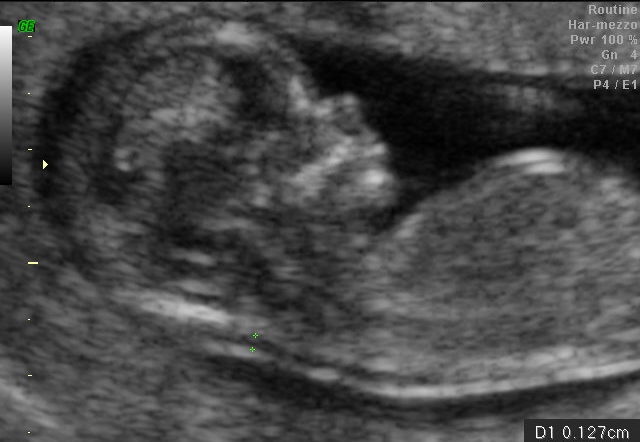

Oggi però vogliamo parlare di un esame molto importante che va effettuato nei primi tre mesi dal concepimento e serve per conoscere possibili malformazioni del feto.